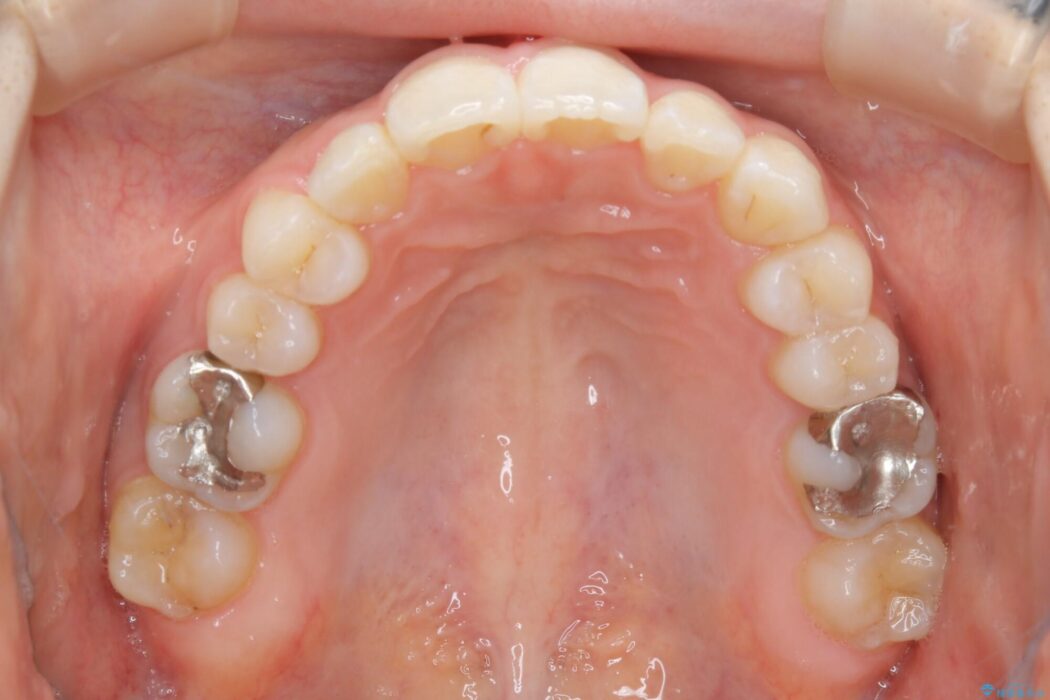

【20代女性】生まれつき歯の本数が足りない先天欠如を治療する

診査したところ叢生だけでなく生まれつき永久歯の欠損、いわゆる先天欠如により歯の本数が少ないため噛み合わせなどにも影響が出ている状態でした。

特殊な状況からの矯正治療となるため、抜歯する本数や位置、歯列を整えるにあたって必要なスペースの確保を慎重に計画し、インビザライン コンプリヘンシブパッケージでのマウスピース矯正を行いました。

笑った時の歯の見た目がきれいになりとても喜んでいただけました。